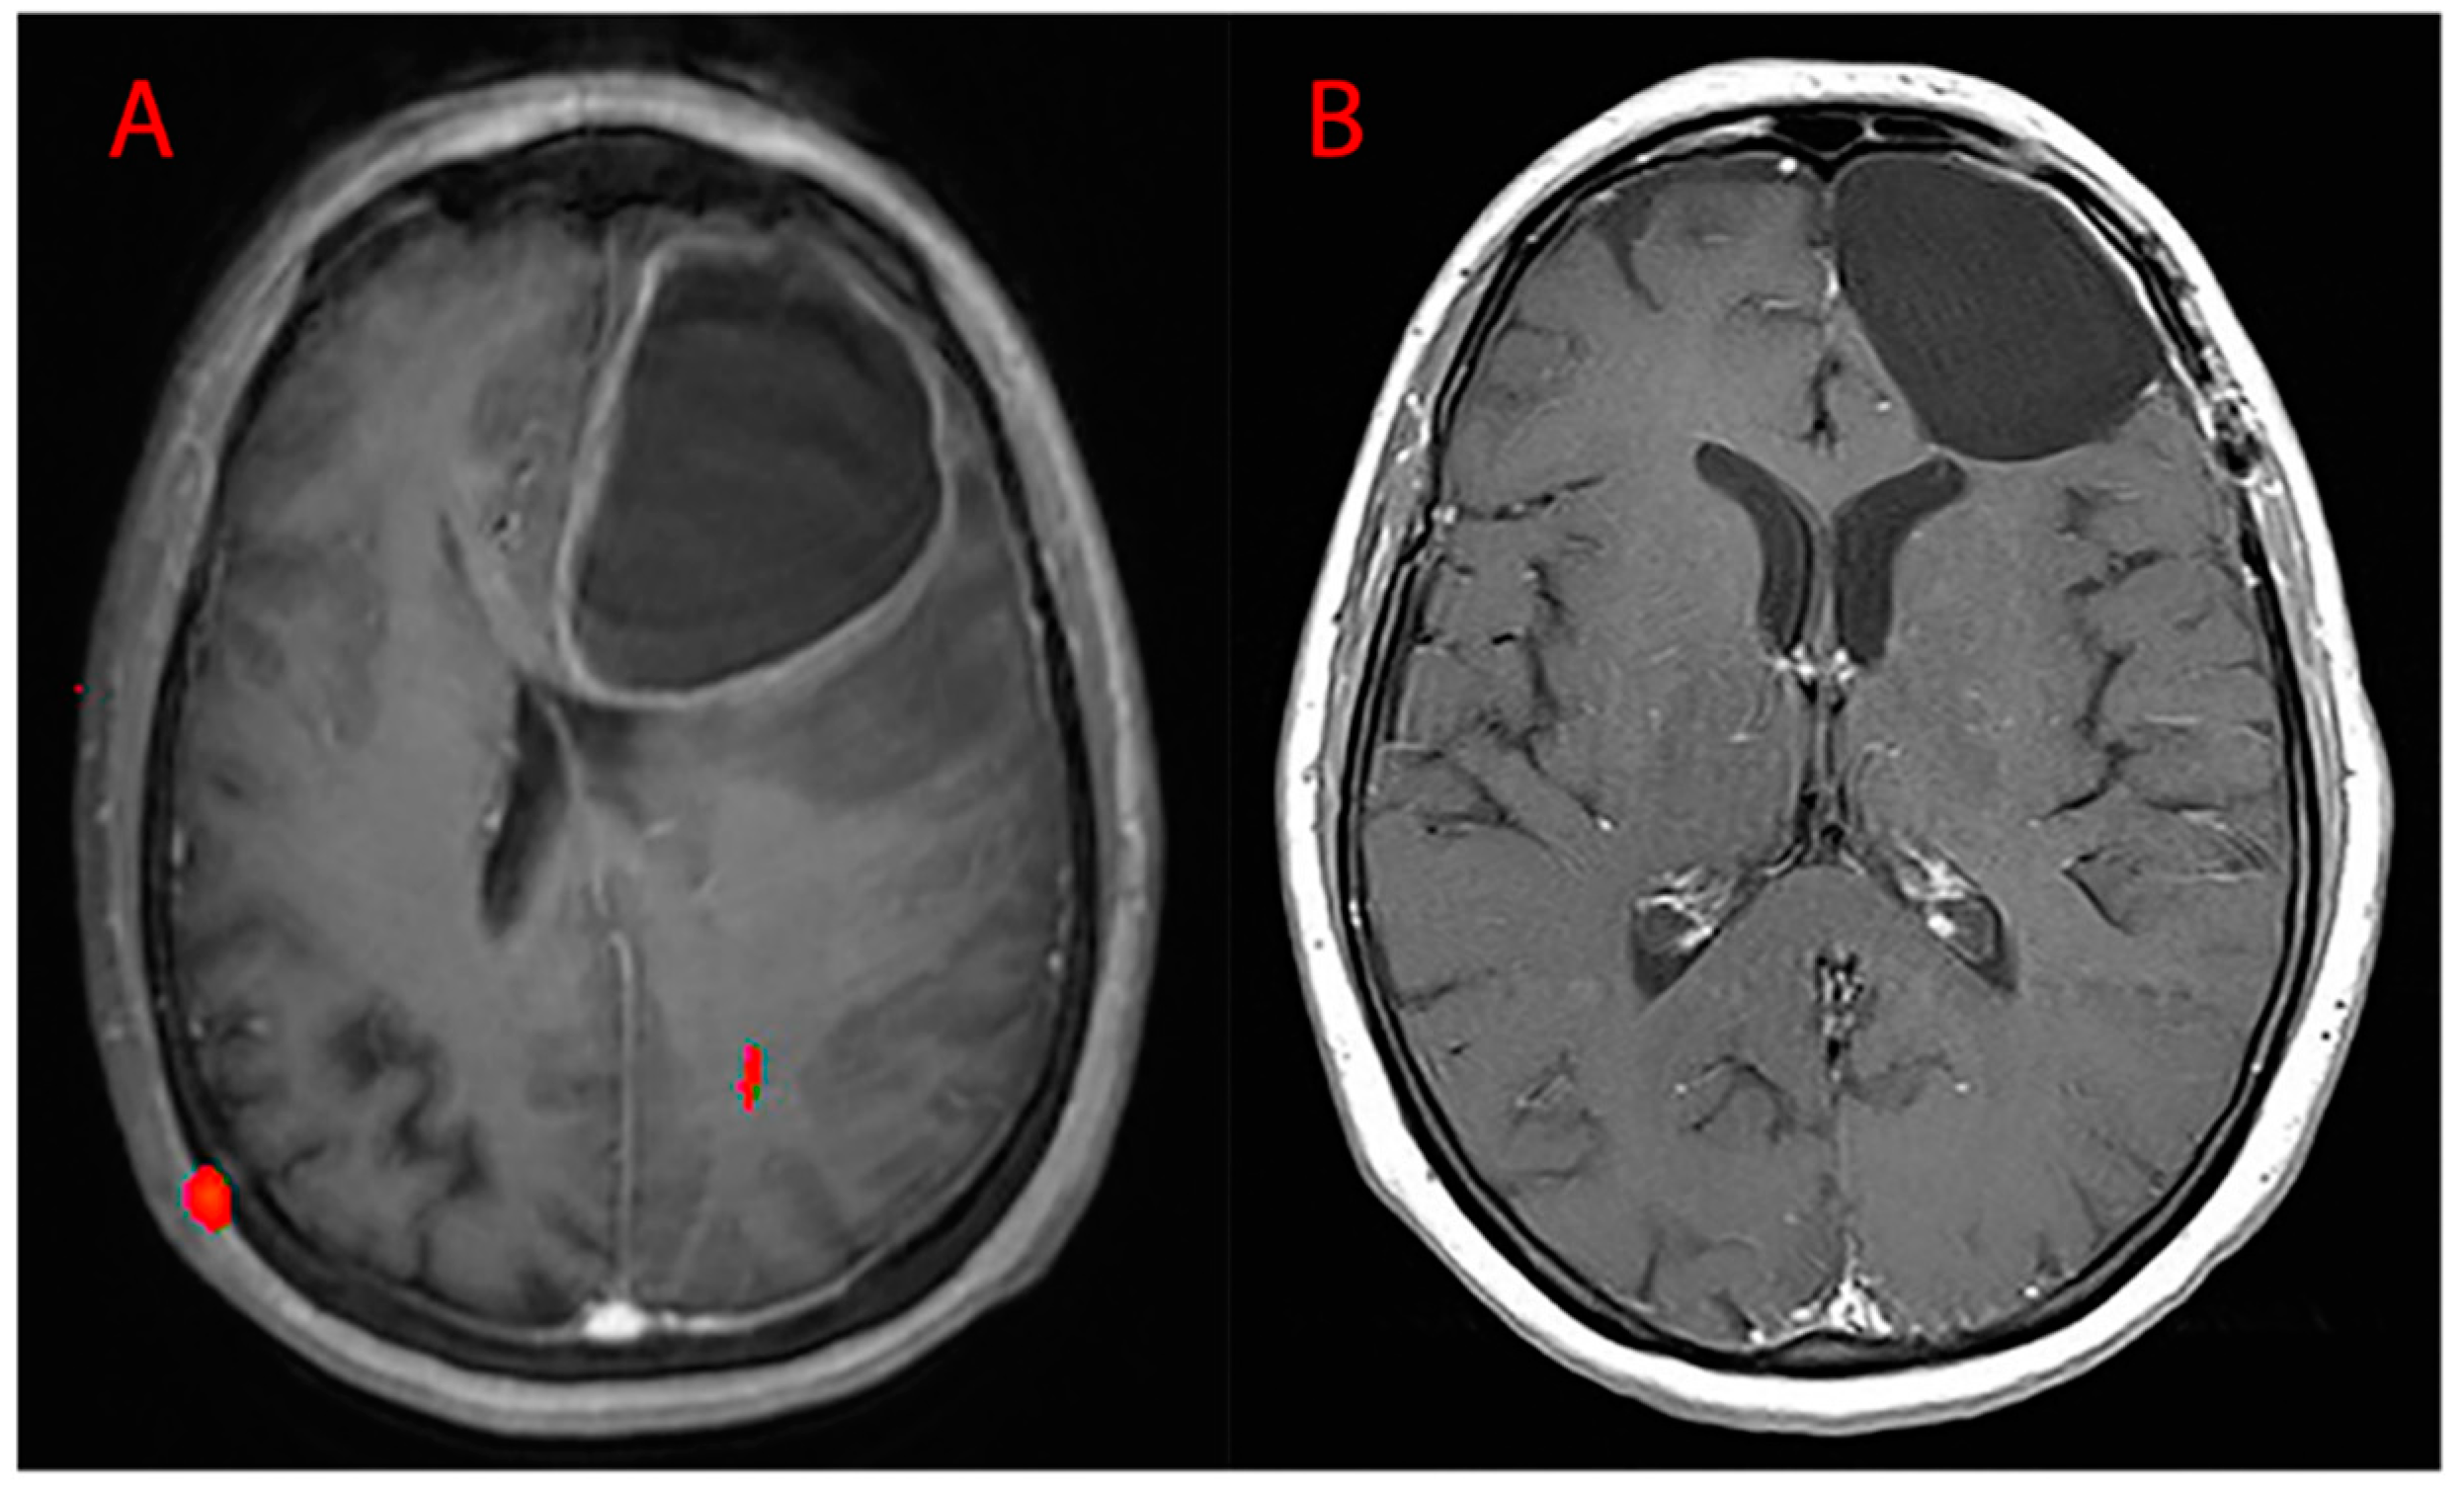

Surgery was performed by the same first operator with the aid of the following: neuronavigation system, intraoperative ultrasound, ultrasound aspirator (CUSA-CAVITRON®), thulium laser, and intraoperative neurophysiological monitoring. Of the procedures, 19.40% were conducted in awake surgery so as to monitor, real-time, the functions of the patient during surgery in eloquent areas. GTR (Figure 9) was performed in 85.95% of cases, while STR (Figure 10) in the residual 14.05%. Partial resections (resection < 90%) and biopsies were not included. Our follow-up consisted of radiological evaluation through brain MRI with gadolinium 20 days after surgery and subsequent clinical reevaluation. Cases of recurrence were also treated in our department: 66.54% of patients underwent a second procedure and 24.95% underwent three.

Figure 9.

MRI T1WI axial sections. (A) Preoperative left frontal lobe GBM and (B) postoperative images (absence of residual disease, GTR).